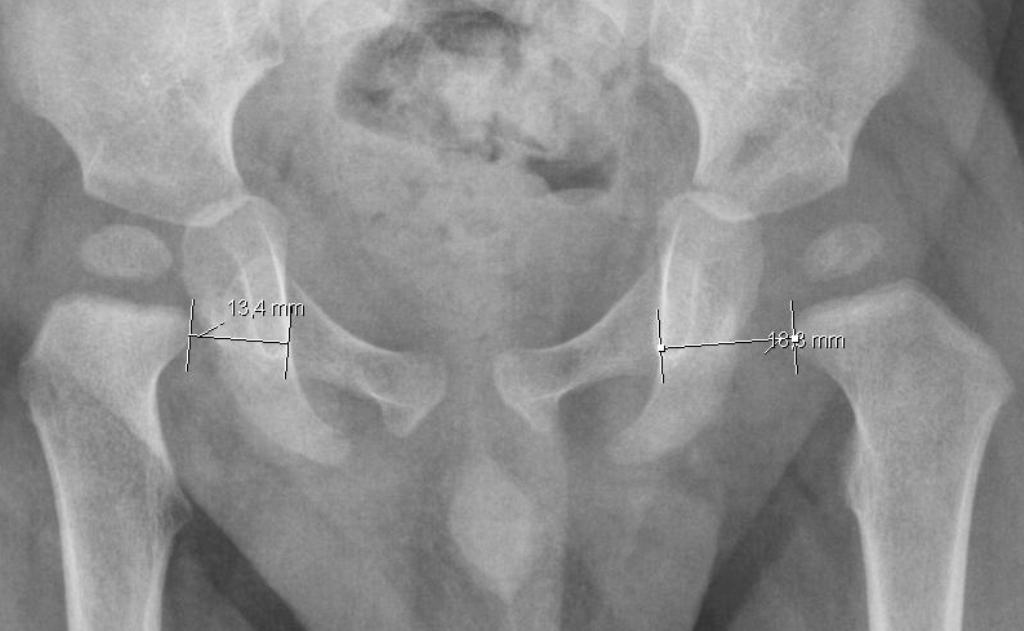

From radiologyassistant.nl